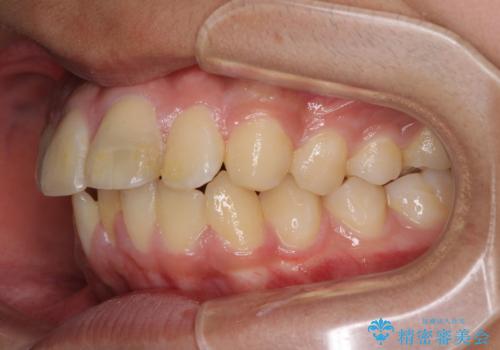

膨らんだ口元 ワイヤー装置での抜歯矯正

- 口元の突出感を気にして来院された患者様です。

上下前歯が著しく前突している状態であったので、上下左右の第1小臼歯4本を抜歯し、ワイヤー装置にて矯正治療を行うこととしました。

舌の突出癖により、前突になったと考えられたため、舌のトレーニングをしっかりと行うよう指導しました。